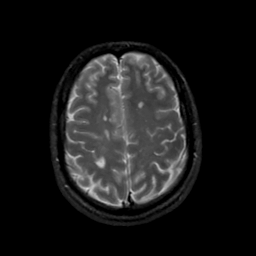

MR Study #20 October 6, 1991 -- Slice #38

[Home][Help][Clinical][Tour 1][Tour 2] Slice 38